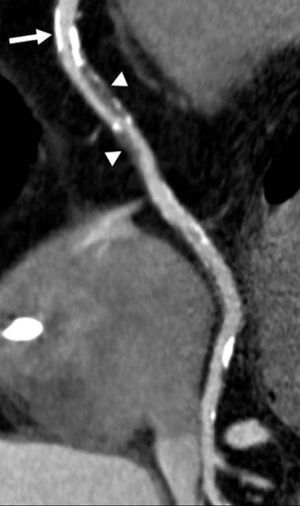

People with obstructive sleep apnea have a higher risk of developing coronary atherosclerosis and coronary artery disease, according to a study presented Tuesday at the annual RSNA meeting.